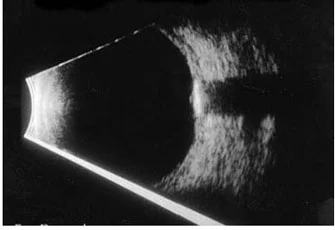

Ocular Ultrasound

used for - for assessment posterior segment - its whats posterior lens espicially in opaque media;

opacity - cataract